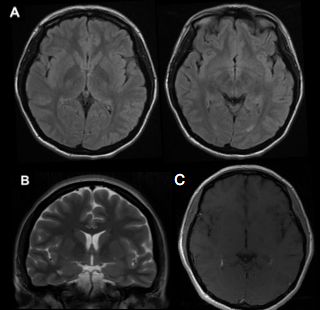

A cerebral MRI showed no alterations in the brain parenchyma nor abnormal enhancements. Lymphocytic pleocytosis of 57 cells/ mm3 was observed in the cerebrospinal fluid (CSF), with a negative result of the Polymerase Chain Reaction (PCR) assay for herpes simplex virus.

Figure: (A) Axial T2-weighted sequence brain MRI with attenuated fluid inversion recovery (FLAIR) without alterations in cerebral parenchyma (B) Coronal T2-weighted sequence without alterations (C) Axial T1-weighted sequence with contrast rules out abnormal enhancements.